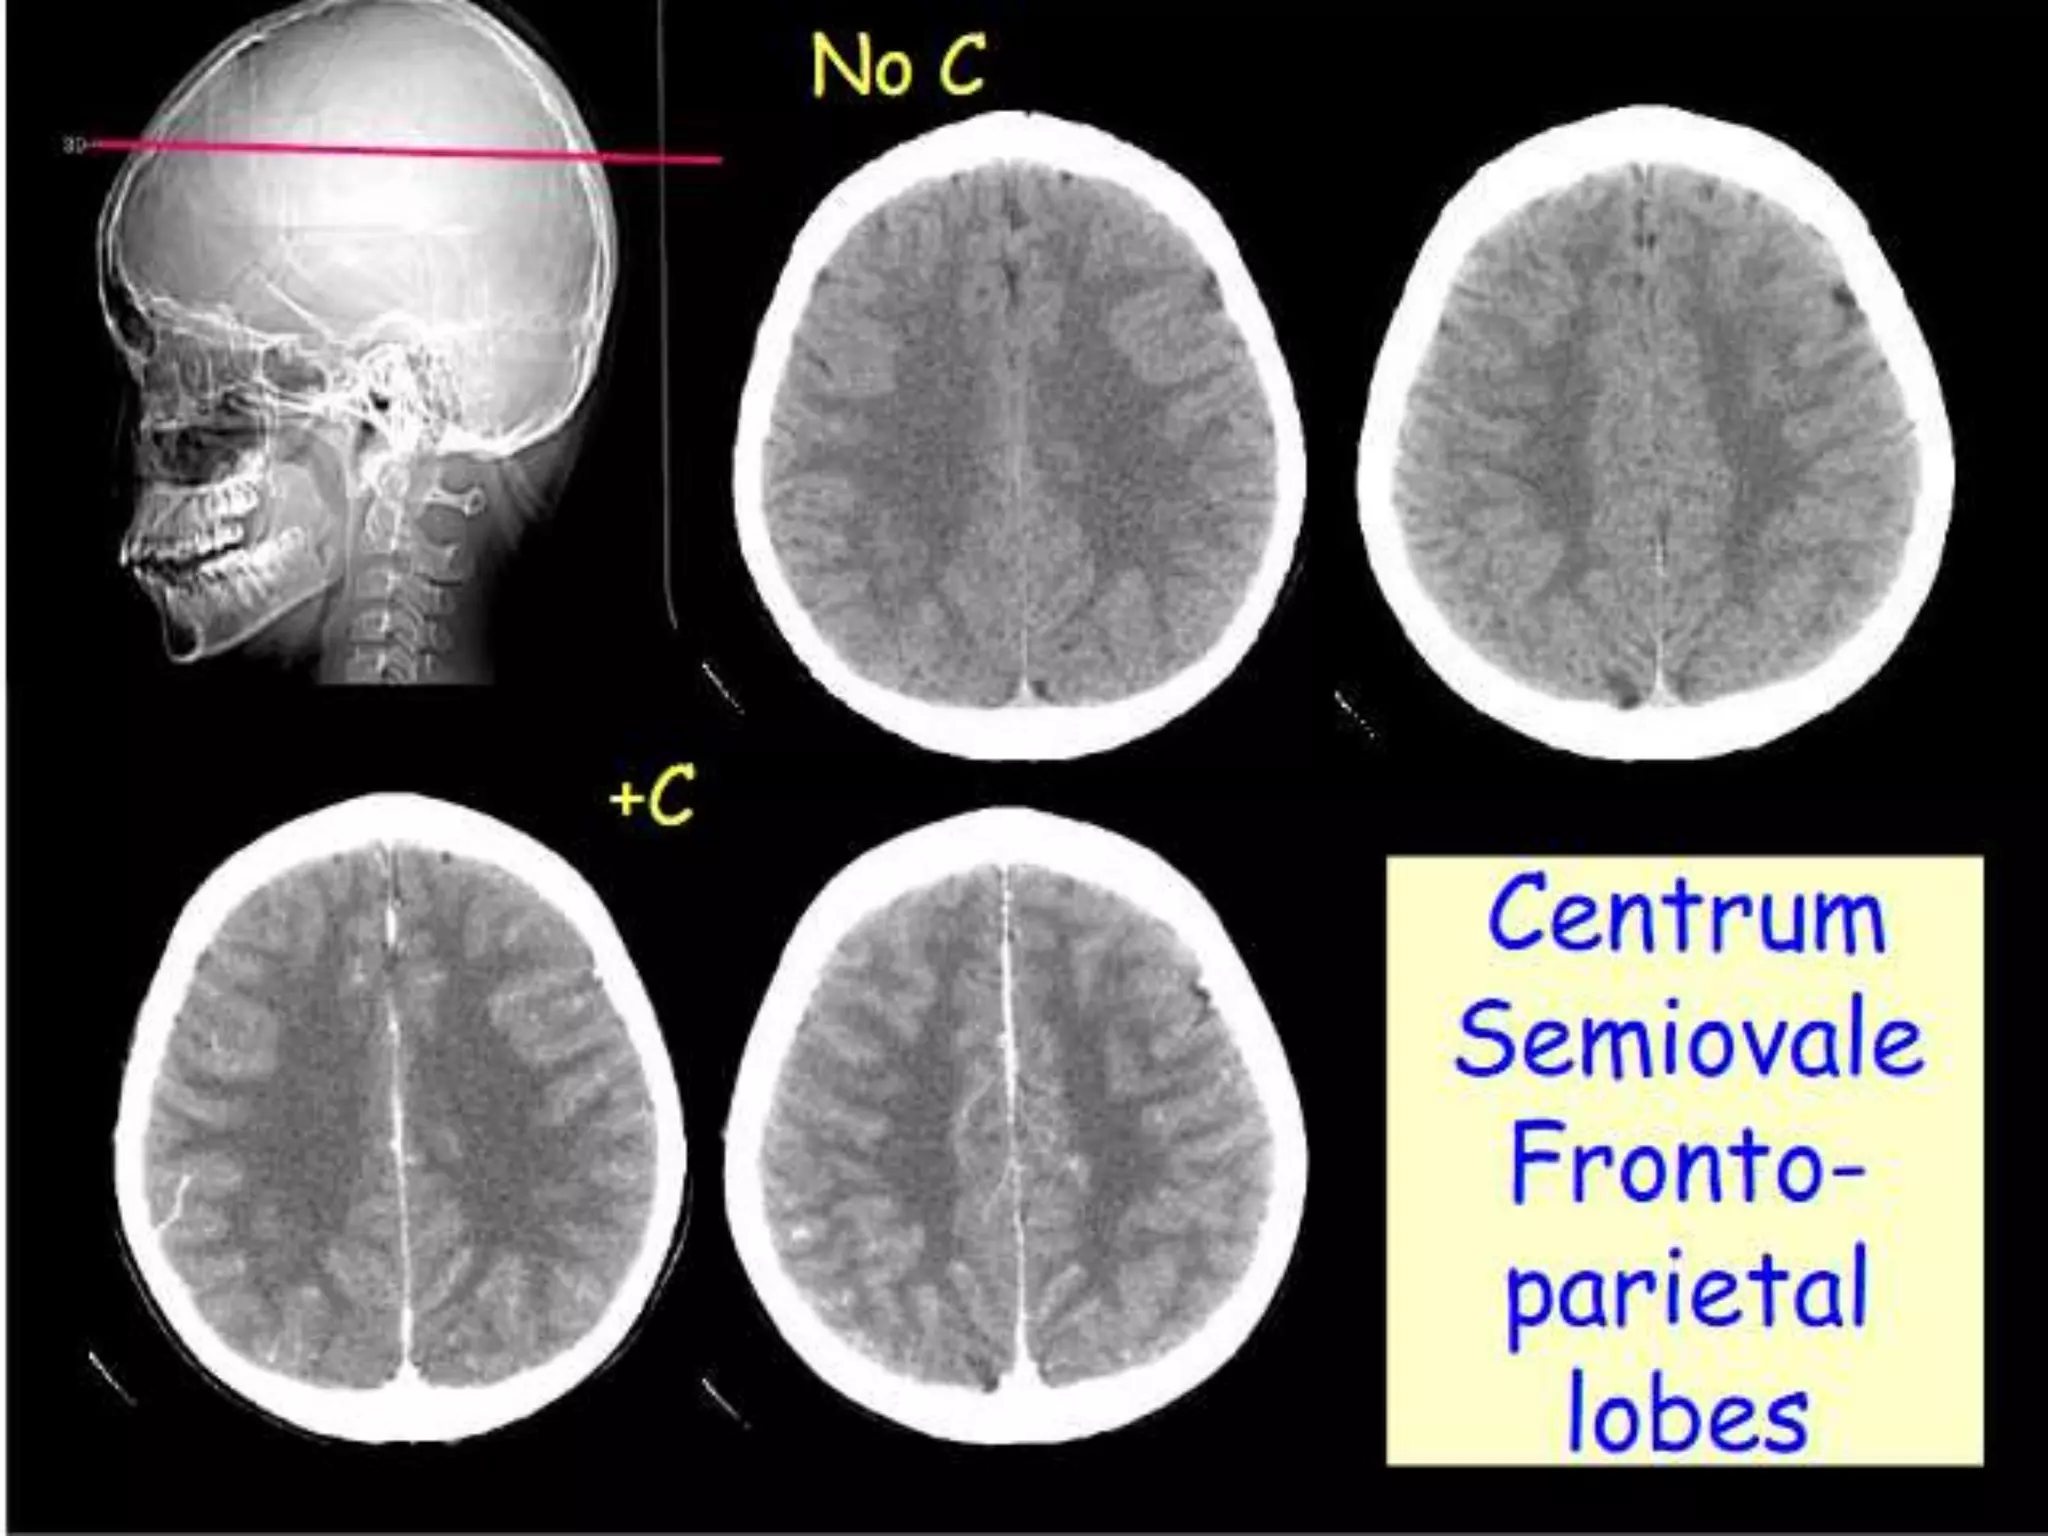

CT scans are performed with a 15- to 20-degree angulation to

the canthomeatal line at 8-mm increments. MRI scans are

generally obtained parallel to the AC-PC line in the axial plane

with 6-mm slice thickness. Using the sagittal view, the coronal

sections are acquired parallel to the brain stem, and the

sagittal sections are obtained perpendicular to the axial

section.

Sectional Anatomy: NormalAxial CT and MRI Anatomy. On CT and MR scans, the brain has been briefly viewed in infratentorial and supratentorial sections, as described below. CT scans are performed with a 15- to 20-degree angulation to the canthomeatal line at 8-mm increments. MRI scans are generally obtained parallel to the AC-PC line in the axial plane with 6-mm slice thickness. Using the sagittal view, the coronal sections are acquired parallel to the brain stem, and the sagittal sections are obtained perpendicular to the axial section. On MRI studies, cranial nerves IX and X can be demonstrated at this level because they emerge from the postolivary sulcus. The posterior aspect of the cerebellar hemispheres is outlined by the inferior portion of the cisterna magna.